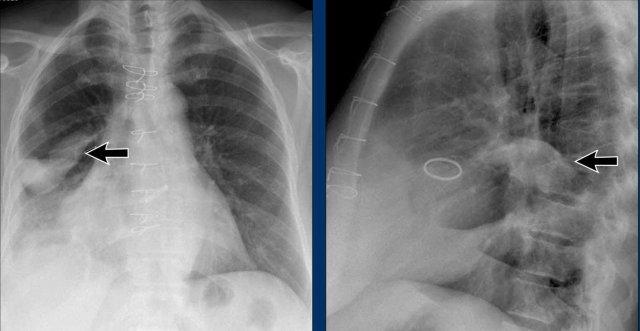

Giãn Thất Phải

Hãy phân tích phim X-quang ngực tư thế thẳng và nghiêng trước, sau đó tiếp tục đọc.

Hình ảnh

- X-quang ngực cho thấy tim to mức độ nặng, chủ yếu do giãn thất phải (mũi tên vàng trên tư thế nghiêng).

- Cung động mạch chủ nhỏ (mũi tên xanh dương), kèm giãn thân động mạch phổi và động mạch phổi phải thùy dưới.

- Các dấu hiệu này gợi ý luồng thông trái-phải với tăng áp động mạch phổi thứ phát.